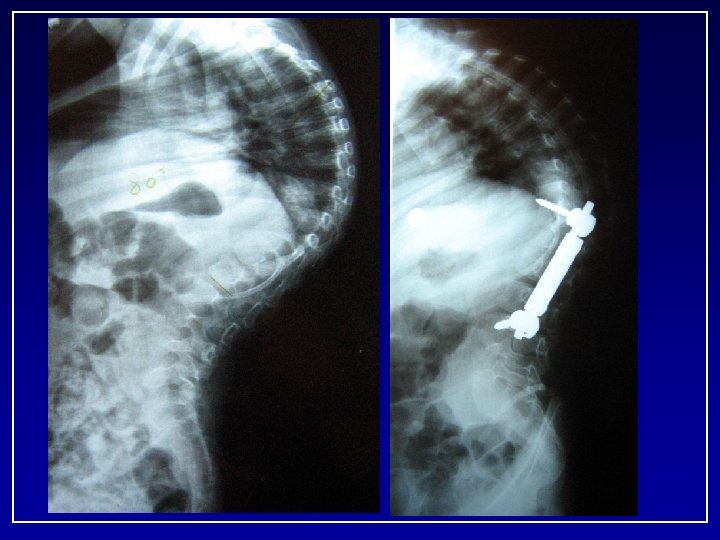

C. C. • 9+7 yrs Boy • Multiple congenital anomalies – Tracheomalacia(s/p tracheostomy, g-tube) – Normal neuro/development milestones – History of multiple pneumonia’s • Initially presented 3/01 at age of 2. 5 yrs • 20° curve progressed to 68° • Failed non operative treatment x one year

Progression 134 128 33 86° 2+6 103

CC 2+6 M.

13 months FU